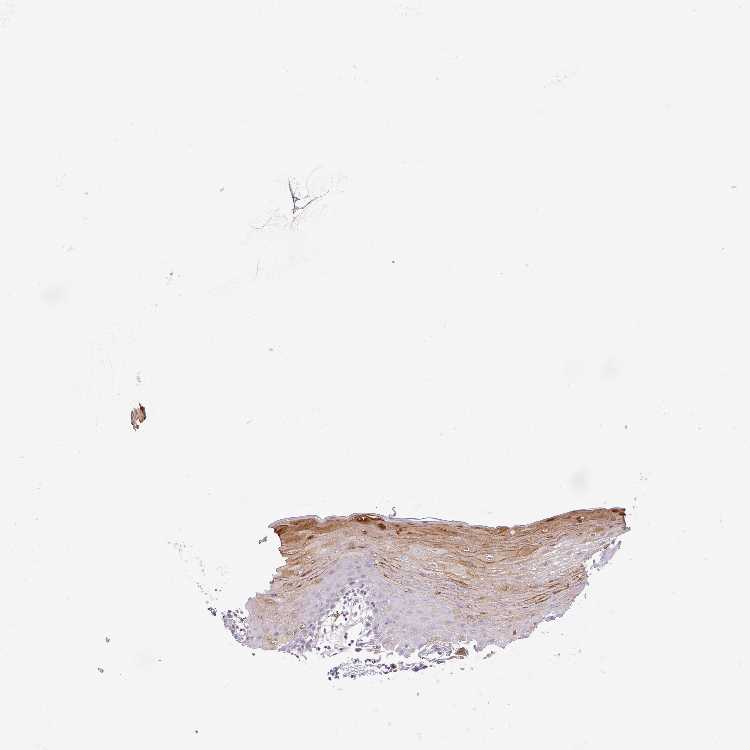

TISSUE PRIMARY DATA ORAL MUCOSA Show tissue menu

ORAL MUCOSA - Antibody stainingi

Antibody staining in the annotated cell types in the current human tissue is reported as not detected, low, medium, or high, based on conventional immunohistochemistry profiling in selected tissues. This score is based on the combination of the staining intensity and fraction of stained cells.

Each image is clickable and will lead to virtual microscopy that enables deeper exploration of all samples and also displays staining intensity scores, fraction scores and subcellular localization as well as patient and tissue information for each sample.

Antibody HPA053129Antibody HPA060974

Squamous epithelial cells MediumNot detected